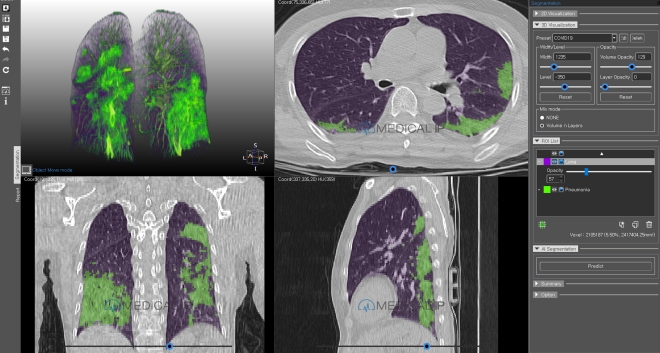

이어 메디컬아이피 박상준 대표가 ‘인공지능 강화 3D 프린팅 기술로 생명을 살릴 수 있습니다’는 주제로 다음 발표를 이었다. 박상준 대표는 “10여년 전 대학의 연구소에서 3D프린팅을 처음 접했다. 거대하고 비싼 장비였기에 사용에 부담감을 느꼈다”고 말했다.

박 대표는 “이후 3D프린팅 기술이 대중화의 흐름을 타고 저렴해졌지만, 여전히 3D프린팅 작업의 가장 큰 장애물은 다양한 비용에서 문제가 발생하며, 이는 의료 분야에서 특히 두드러진다”고 덧붙였다.

오늘날 의료 분야에 적용되는 3D프린팅은 워크플로우 소프트웨어 플랫폼을 활용함으로써 3D프린팅 작업에 소요되는 시간 비용, 다수의 연구원이 함께 움직이는 기회비용, 그리고 재료· 기계 활용 등에 대한 경제적 비용을 해결하고 있다.

AI 기술 기반의 의료용 3D프린팅 플랫폼은 3D프린팅 기술을 활용하는 의료진의 수술 전 의사결정능력과 정확성 및 효율성을 향상시킬 수 있으며 실제 의료현장에서 생명을 살리는 사례를 만들고 있다.

박상준 대표는 “전문의의 경험과 노하우를 집약한 AI를 활용하게 되면서 영상을 구현하기 더 쉬워졌다. 다양한 기능을 활용해 실제와 동일하게끔 구현할 수 있다. 360° 돌려보거나 단면을 잘라보는 등 디테일한 표현도 가능하다”고 말했다.

3D프린팅되기 전 추출된 데이터는 비주얼 프린팅이라는 기술로 현실감 있게 모델링된 장기구조물로 표현되며, 이 정보는 웹으로 연동될 뿐 아니라 모바일로 손쉽게 공유된다.

박 대표는 “맞춤형 의료 3D프린팅은 세 가지가 핵심이다. 의료영상 분석과 모델링 기술, 소재·재료에 대한 전문성. 병원·의료진과의 소통이다. 맞춤형 의료 3D프린팅은 세 가지 모두가 확보돼야 하는 기술 집약 맞춤형 모델이라 할 수 있다”고 말했다.

▲MEDIP Pneumovid(출처 : 메디컬아이피)